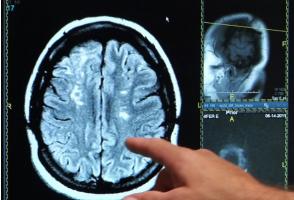

TROUBLES MENTAUX et risque accru de maladies cardiaques

Certains troubles mentaux augmentent notamment et considérablement le risque de maladie cardiaque, conclut cette équipe de l’Université Emory Health Sciences (Atlanta), qui démontre ici, par le menu et dans le Lancet Regional Health – Europe, le lien étroit entre santé cardiovasculaire et santé mentale.